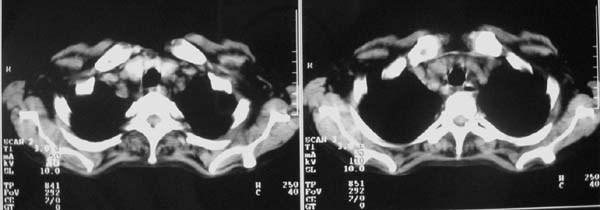

以下是引用zjzjr在2007-9-20 12:29:00的发言:[br]双肺磨玻璃改变,考虑肺水肿.

以下是引用yangzongshan在2007-9-20 18:29:00的发言:[br]两肺毛玻璃样改变,其内可见肺纹理影,无胸腔积液,故考虑肺泡蛋白沉积症

以下是引用276894491在2007-9-20 13:40:00的发言:[br]考虑肺水肿;外源性过敏性肺炎不排除。

以下是引用逸风在2007-9-20 20:45:00的发言:[br]两肺磨玻璃样改变,临床病史短,发热,考虑病毒感染合并右肺代偿性肺气肿.待排肺水肿,病史短,不支持肺泡蛋白沉着症.